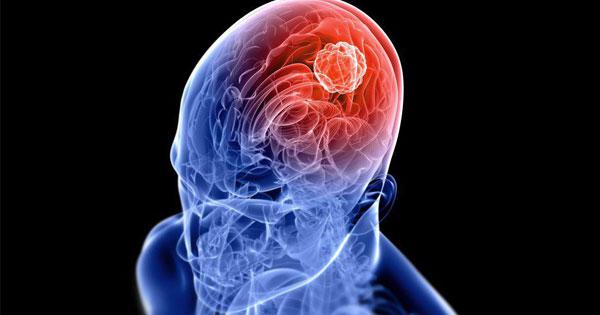

รวมเรื่องน่ารู้เกี่ยวกับเนื้องอกในสมอง ที่ส่งผลกระทบต่อการทำงานของระบบสมอง และระบบประสาท มาอ่านข่าวเกี่ยวกับสุขภาพ พร้อมประเด็นที่เกี่ยวข้องล่าสุด

รวมเรื่องน่ารู้เกี่ยวกับเนื้องอกในสมอง ที่ส่งผลกระทบต่อการทำงานของระบบสมอง และระบบประสาท มาอ่านข่าวเกี่ยวกับสุขภาพ พร้อมประเด็นที่เกี่ยวข้องล่าสุด

เนื้องอกในสมอง มะเร็งสมอง สังเกตได้จากอาการปวดหัวเรื้อรัง

เนื้องอกในสมอง มะเร็งสมอง สังเกตได้จากอาการปวดหัวเรื้อรัง